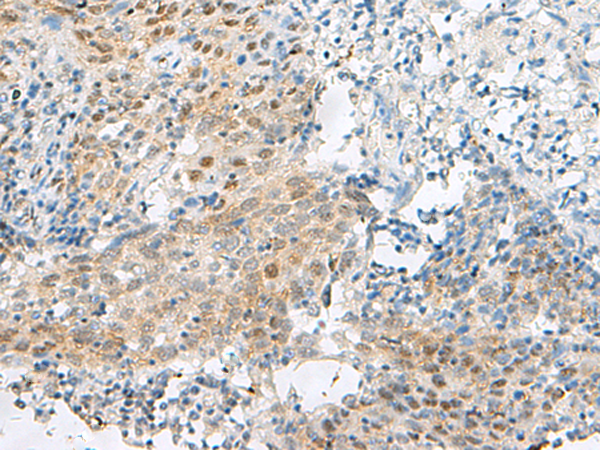

分类: 科研抗体货号: P02870别名: TASSC; HSPC299; NIPSNAP4应用: IHC反应种属: Human